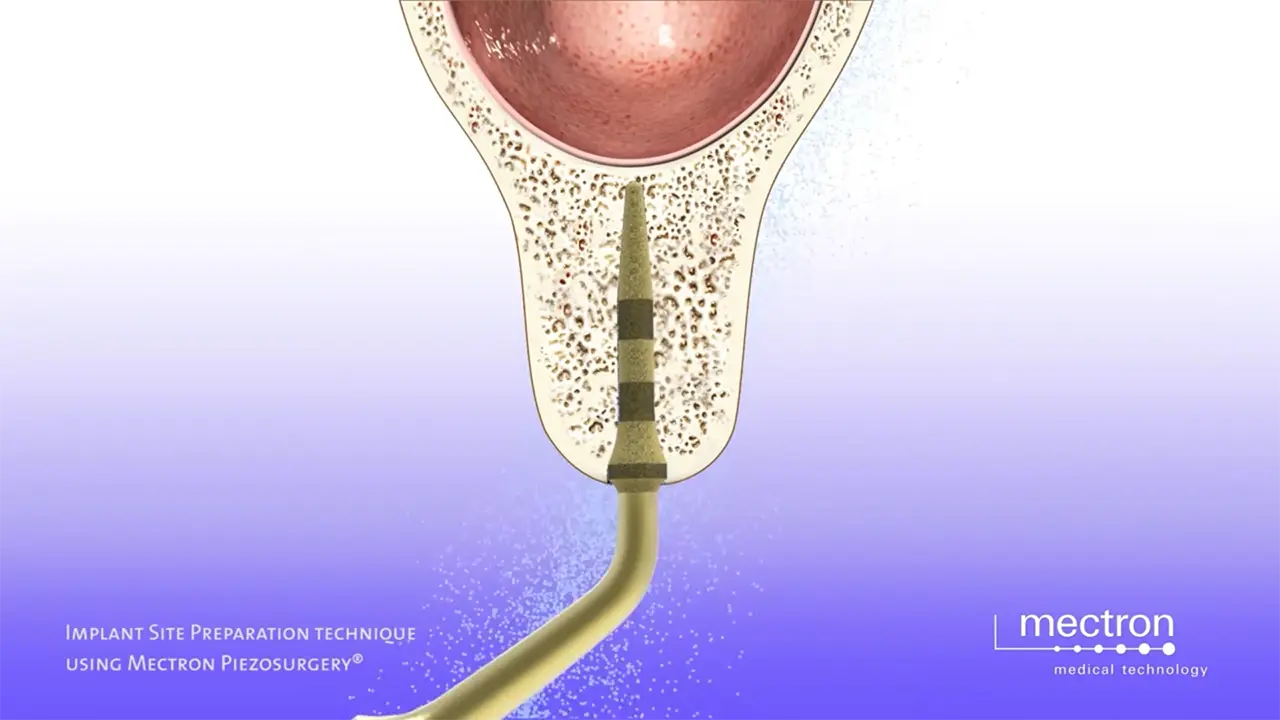

PIEZOSURGERY® Implant site preparation

Prof. Tomaso Vercellotti

Ultrasonic preparation of the implant site – UISP technique